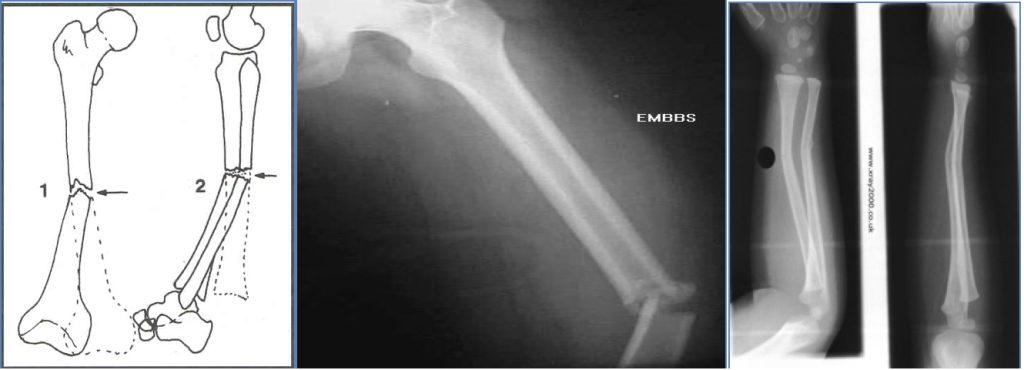

Describing a Fracture on X-Ray

- Fracture or Dislocation?

- Which Bone?

- Location of Injury?

- Type of Fracture?

| Type | Description |

|---|---|

| Complete | Full separation of bone fragments |

| Incomplete | Partial separation (e.g. greenstick in children) |

| Transverse | Perpendicular to bone axis |

| Linear | Parallel to bone axis |

| Oblique | Angled across bone axis |

| Spiral | Curved pattern (often from twisting) |

| Greenstick | Partial break in flexible bone (common in children) |

| Comminuted | ≥3 bone fragments |

| Compacted | Fragments crushed into each other (common in hip) |

- Displacement?

- Described as % of offset between fragments (e.g. 50%, 100%)

- Angulation?

- Measured in degrees, e.g. “30° lateral angulation of distal femur”